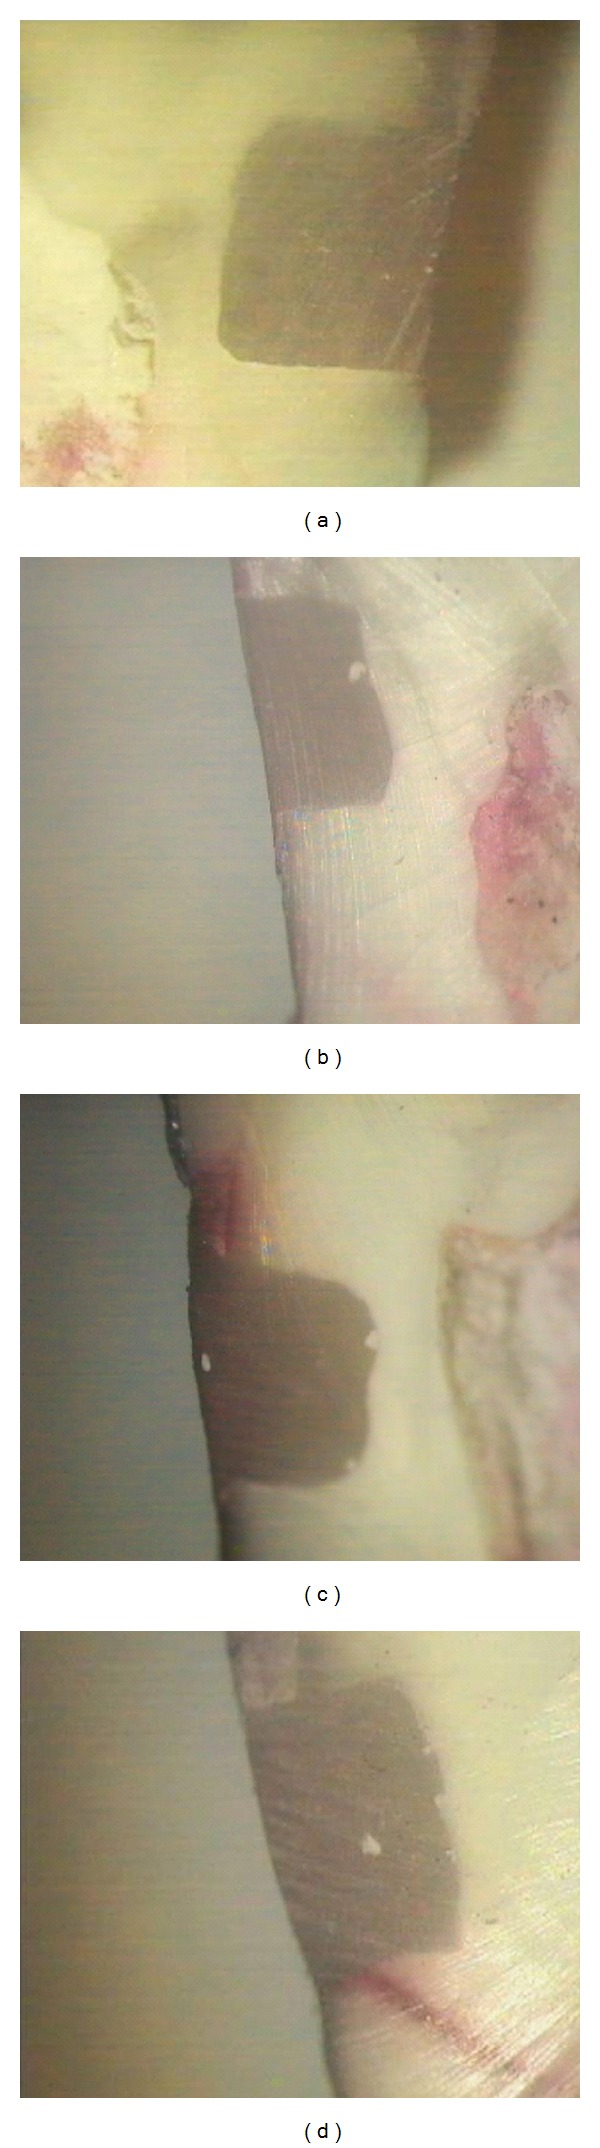

Introduction. Sealing abilities of two self-etch adhesives were evaluated after two aging processes: storage in water and thermocycling. Materials and Methods. Cl V cavities were prepared on the buccal and lingual aspects of 48 human premolars, with cervical margins 1 mm below the CEJ. Clearfil Protect Bond (CPB) and BeautiBond (BB) (two-step and one-step self-etch adhesives, resp.) were applied, each to half of the cavities and restored with composite resin. Each group was randomly subdivided into 4 subgroups (n = 12) and evaluated for dye penetration after 24 hours, after 3000 thermocycling rounds, after a 6-month water storage, and after 3000 thermocycling rounds plus 6-month water storage, respectively. Data was analyzed using SPSS 11.5 and Kruskal-Wallis and Mann-Whitney U tests (α = 0.05). Results. There were no significant differences in enamel and dentin microleakage between the adhesives (P = 0.683; P = 0.154). Furthermore, no significant differences were observed in enamel microleakage of each one of CPB and BB (P = 0.061 and P = 0.318, resp.). However, significant decrease was observed in subgroups 3 and 4 (P = 0.001) for CPB dentinal margins. Conclusion. In this study, limited aging procedures had no influence on marginal integrity of composite resin restorations bonded with self-etch adhesives of CPB and BB. Furthermore, CPB dentinal sealing improved after aging.